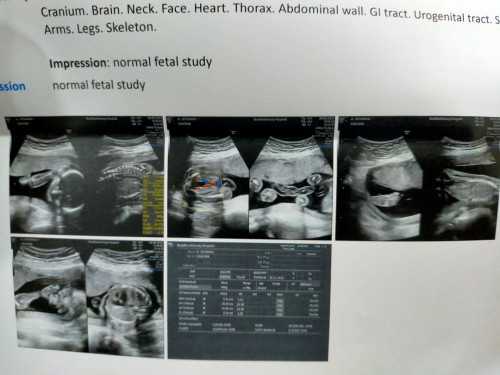

38+4w กำหนดคลอด 6พ.ย. มีแม่ๆบ้านไหน หมอตรวจปากมดลูก แล้วมีมูกเลือดออกบ้างมั้ยค่ะ หมอขว้านมดลูกเจ็บมากๆๆ คุณหมอบอกว่ากับบ้านไปอาจมีมูกเลือดเยอะหน่อย แต่ยังไม่หน้าคลอด ปากมดลูกเปิด 2 เซนแล้วค่ะ หมอให้เวลาอาทิตย์นึงคลอด บ้านนี้ตรวจมาแล้วมีมูกเลือดออกนิดหน่อย ไม่ถึงกับเยอะ #คุณแม่ๆช่วยแนะนำหน่อยค่ะ #ท้องแรกคะ